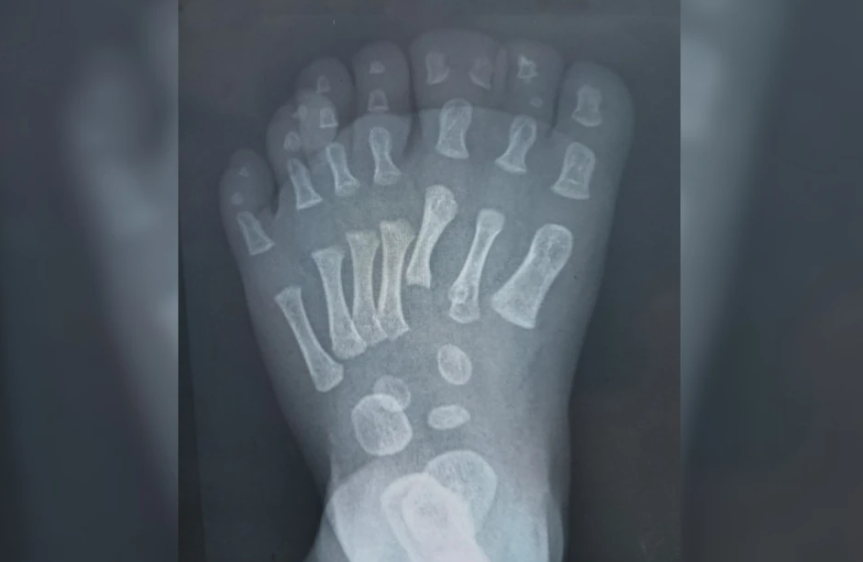

В отделении травматологии Ивано-Матренинской детской больницы стало больше пациентов с необычными диагнозами - полидактилией (лишние пальцы – Ред.) и синдактилией (сросшиеся пальцы – Ред.). После того как врачи прооперировали малыша с восемью пальцами на ногах, в больницу посыпались звонки от родителей со всего региона.

- В Иркутске врачи прооперировали ребенка с восемью пальцами на ноге